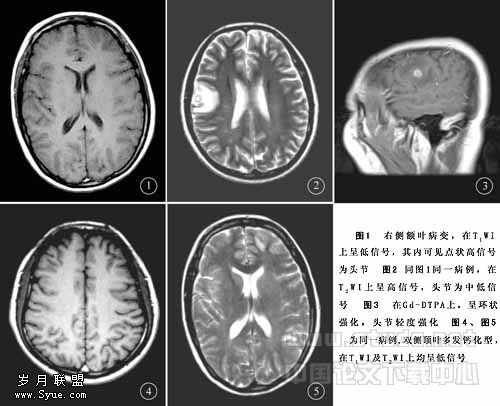

2.3.2 多发小囊型 系多个存活期囊尾蚴并存的表现。MRI表现为双侧大脑皮质区有多个散在分布的小圆形或卵圆形小囊,直径3~8mm,在T1WI上呈低信号,在T2WI上呈高信号,壁内偏心型小点状影为囊虫头节,在T1WI上呈高信号,在T2WI上呈中低信号,见图1、图2,周围水肿不明显。在FLAIR上脑脊液为低信号,而变性囊液为相对高信号。Gd-DTPA增强扫描,囊壁多呈环状强化,少数不强化,头节多呈点状强化,少数可不强化,见图3。

2.3.7 钙化型 系囊尾蚴死亡后被机化,形成纤维组织或钙化的表现。MRI表现为脑实质内多发或单个小病灶,直径一般2~4mm,在T1WI及T2WI上均呈低信号,见图4、图5,周围无水肿带,Gd-DTPA增强扫描无强化。

2.3.8 脑室型 囊尾蚴寄生于脑室内,可引起阻塞性脑积水。MRI表现为囊虫所在部位脑室呈不对称性增大,在T1WI上呈低信号,在T2WI上呈高信号,存活期囊虫多较脑实质型虫体体积大,直径可>2cm,囊壁上可见偏心型头节影,在T1WI上呈略高信号,在T2WI上呈低信号。Gd-DTPA增强扫描,囊虫存活期囊壁无强化;退变死亡期囊壁可明显强化。